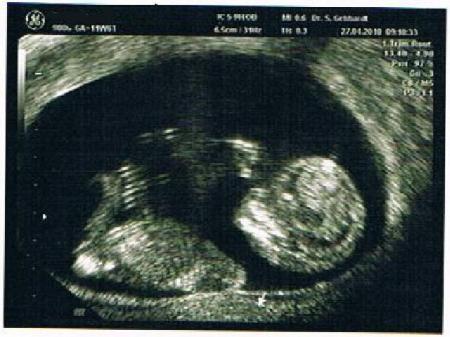

huhu, nach der letzten vorsorge wurde nach ulltraschallbild gefragt hier is es nun und von kopf bis po 5 cm groß

das is aber ein wirklich schönes bild! man sieht so richtig schön das köpfchen!

Hey, das Foto ist wirklich total schön u.Würmchen sieht total glücklich aus ;-) Liebe Grüße..